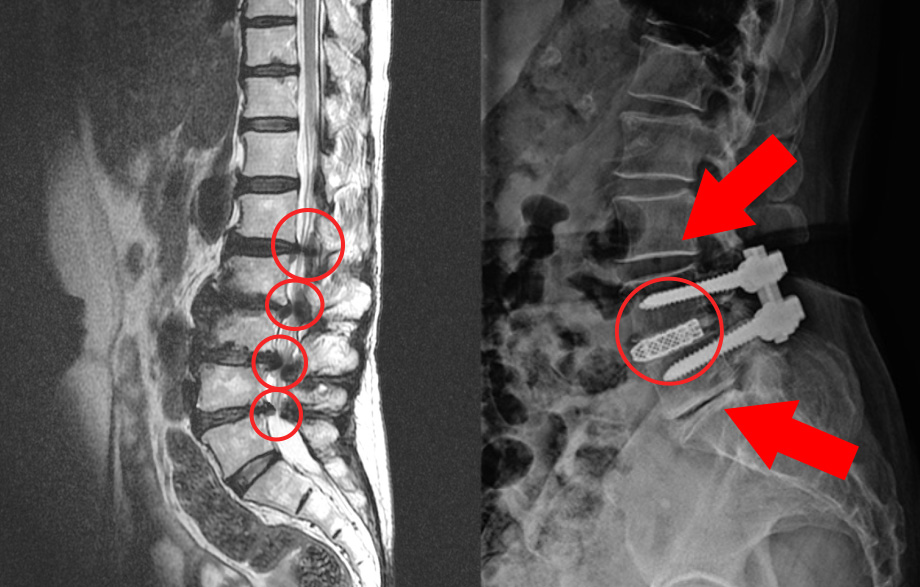

협착증 치료에 대한 잘못된 생각 두 번째, 치료만 하면 끝이라는 생각입니다. 많은 분들이 협착증 치료는 원인을 깨끗하게 해결할 거라고 기대합니다. 그래서 치료만 받으면 다 끝난다고 생각하니까 치료에 대해 조급증을 갖습니다. 그래서 조급하게 치료를 결정하고, 치료를 받고 나면 모든 게 끝날 거라 기대합니다. 이 경우 무엇이 문제가 되느냐? 모든 게 끝났다고 생각하니까 관리를 안 하고, 이게 많은 문제를 일으킬 수 있습니다. 한번 늙어버린 건 다시 젊어지지 않으므로, 치료 후에 어떤 치료를 받고 좋아졌든 지속적인 세심한 관리와 재활운동이 반드시 필요합니다. 치료만 받으면 끝이라고 생각하고 조급함을 가질 경우 생길 수 있는 문제를 먼저 수술 후 발생할 수 있는 문제부터 말씀 드리겠습니다. 협착증 수술은 문제를 일으키는 가장 큰 원인인 퇴행된 척추관 내의 황색인대를 제거하게 되는데, 퇴행이 가장 심한 부분을 수술로 제거하고 나사를 박아 고정시키게 됩니다.

그런데, 보시면 협착증은 이 부분만이 아니라 주변 부분도 다 퇴행되어 있습니다. 그래서 고정술을 한 이후에 이 부분이 구부리지도 펴지도 못하게 되기 때문에 이미 퇴행된 주변 마디에 부담을 주게 됩니다. 주변 마디가 더 많이 구부렸다 폈다가 해줘야 하는 것이죠. 그런데 앞서 말했듯이 협착증 환자는 이미 주변 위아래 마디도 퇴행되어 약해진 상태인데, 추가적으로 부담을 주니까 시간이 흐르면 주변 부위도 문제가 생기게 되는데요. 이것을 인접분절질환이라고 합니다. 일반적으로 척추유합술 후 이러한 문제가 많이 발생하기 때문에 인접분절질환이라는 이름까지 만들어져 있습니다. 이러한 인접분절질환은 특히 수술 후 관리를 잘 못하면 당연히 더 잘 생기기 때문에 유합술을 했다면, 이 인접분절질환이 생기지 않도록 관리를 세심하게 잘 해줘야 합니다.